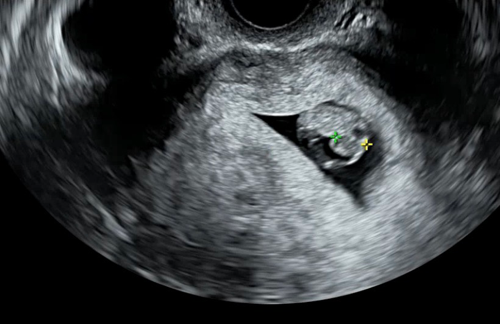

그 사이에 여태 햇살이의 초음파 영상을 하나씩 돌려봤다

햇살이의 콩알부터 시작해서 동그란 링 속의 젤리 곰, 10주 차에 걱정했던 목 투명대 영상의 조그마한 생명체, 정밀 초음파에서 처음으로 본 사람 형체, 그리고 꼬물거림. 입체 초음파의 얼굴.